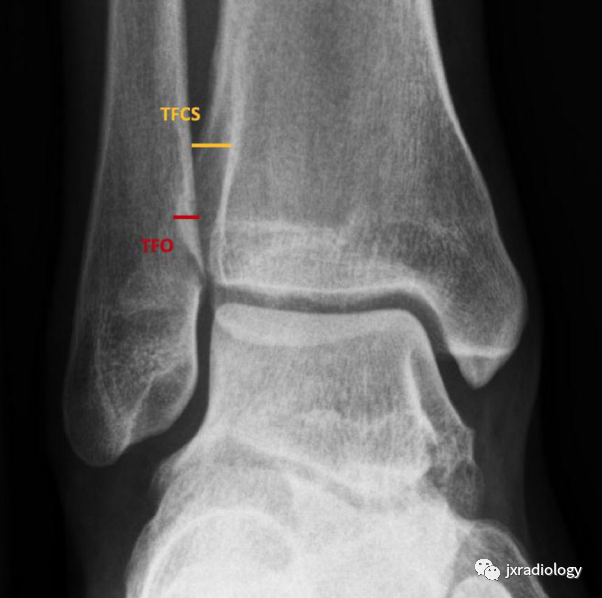

2、正常的踝关节下胫腓联合测量数据:在标准前后位X线片上胫骨远端关节面上1cm水平,下胫腓联合间隙(TFCS)>5mm或胫腓重叠(TFO)在前后位X线片上<10mm,表明存在下胫腓联合损伤。应该进行CT或MRI检查以明确诊断。

下胫腓联合间隙(tibiofibular clear space,TFCS)胫腓骨重叠(tibiofibular overlap,TFO),正常大于6mm